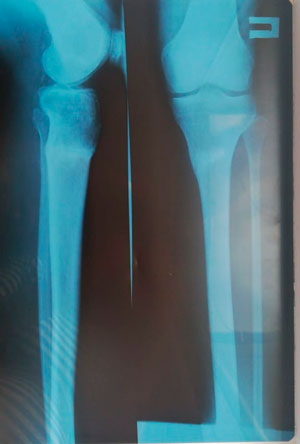

Диагноз: Варусная деформация голеней. Ротация справа.

Дата операции - 07.11.2019г.